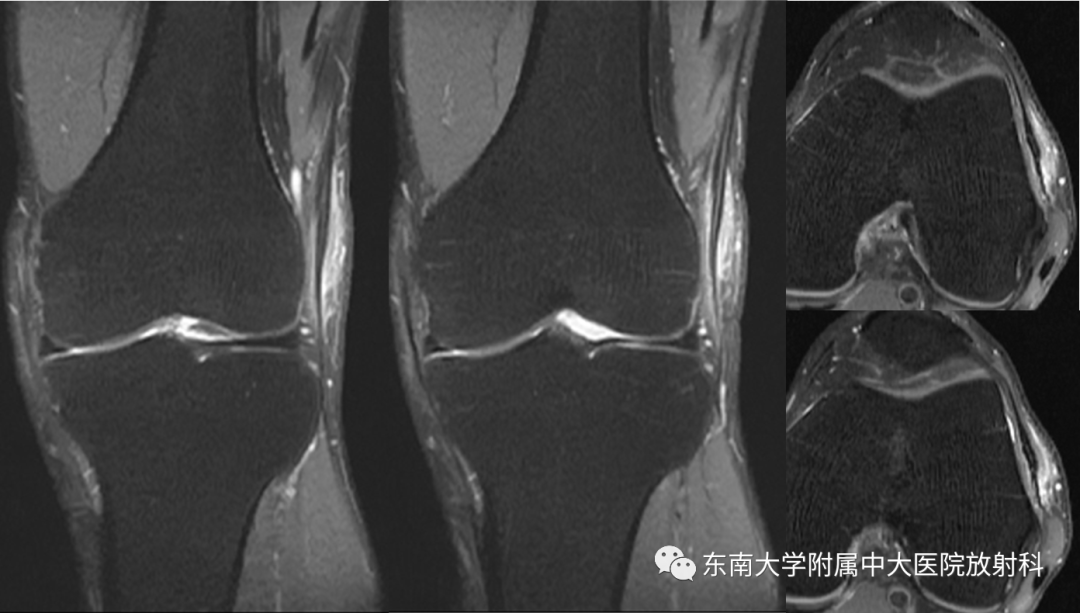

2021-04-26 MR

2022-04-11 MR